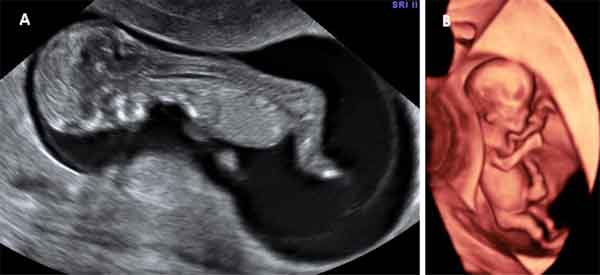

En la semana 11 de embarazo está terminando la etapa embrionaria y muy pronto se pasará a la fetal. La ecografía puede decirnos muchas cosas: si hay malformaciones graves, si falta alguna extremidad, o incluso adelantar el sexo del bebé, porque ya están formados los genitales externos. La embarazada suele entrar en una etapa de mayor estabilidad (menos náuseas y vómitos) a medida que su útero crece.

Ecografía de la semana 11

El tamaño del embrión permite que con la ecografía de la semana 11 se puedan hacer las tres medidas esenciales que nos permiten determinar la edad gestacional. Estas son:

- Las grandes malformaciones embrionarias (cardiacas, cerebrales y abdominales) pueden distinguirse en esta semana con la ecografía. La ausencia de alguna extremidad ya puede verse en la semana 11 de embarazo, siempre que se disponga de ecógrafos de alta resolución.

- Diámetro biparietal (diámetro de la cabeza)

- Longitud del fémur (longitud del muslo)

- Circunferencia abdominal